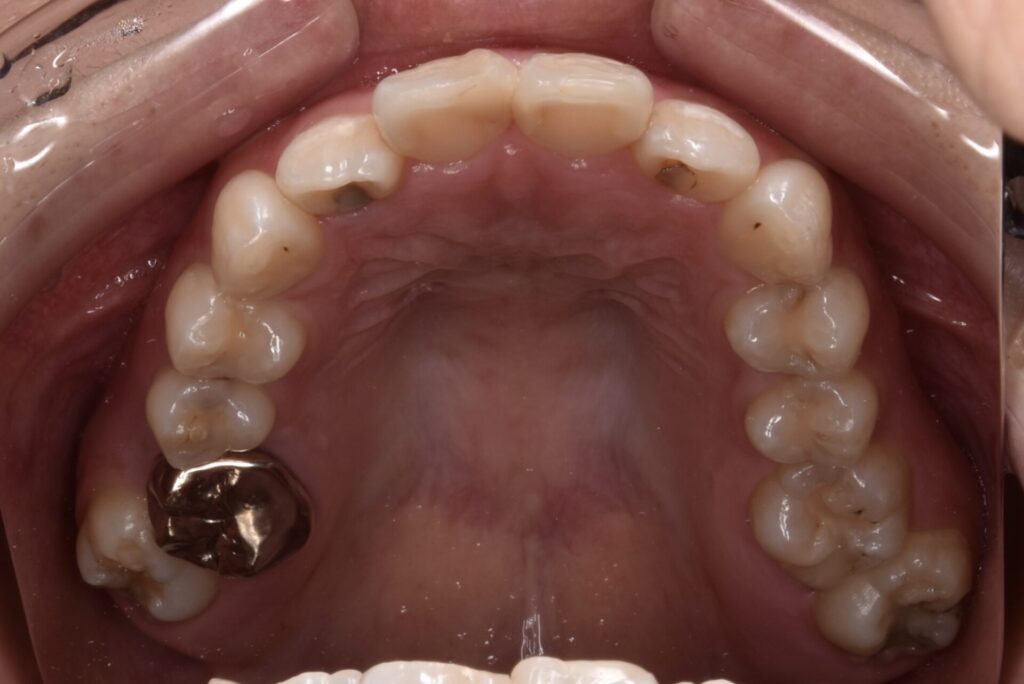

矯正後

矯正はインビザライン モデレートで行っています。追加アライナーなし 途中妊娠出産のため来院間隔が空いています。